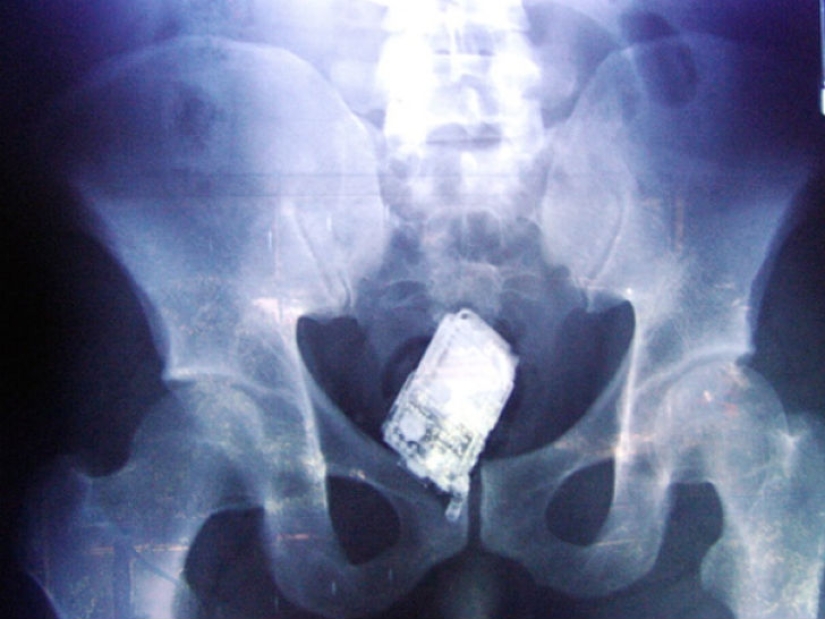

And prisoners also swallow cell phones.